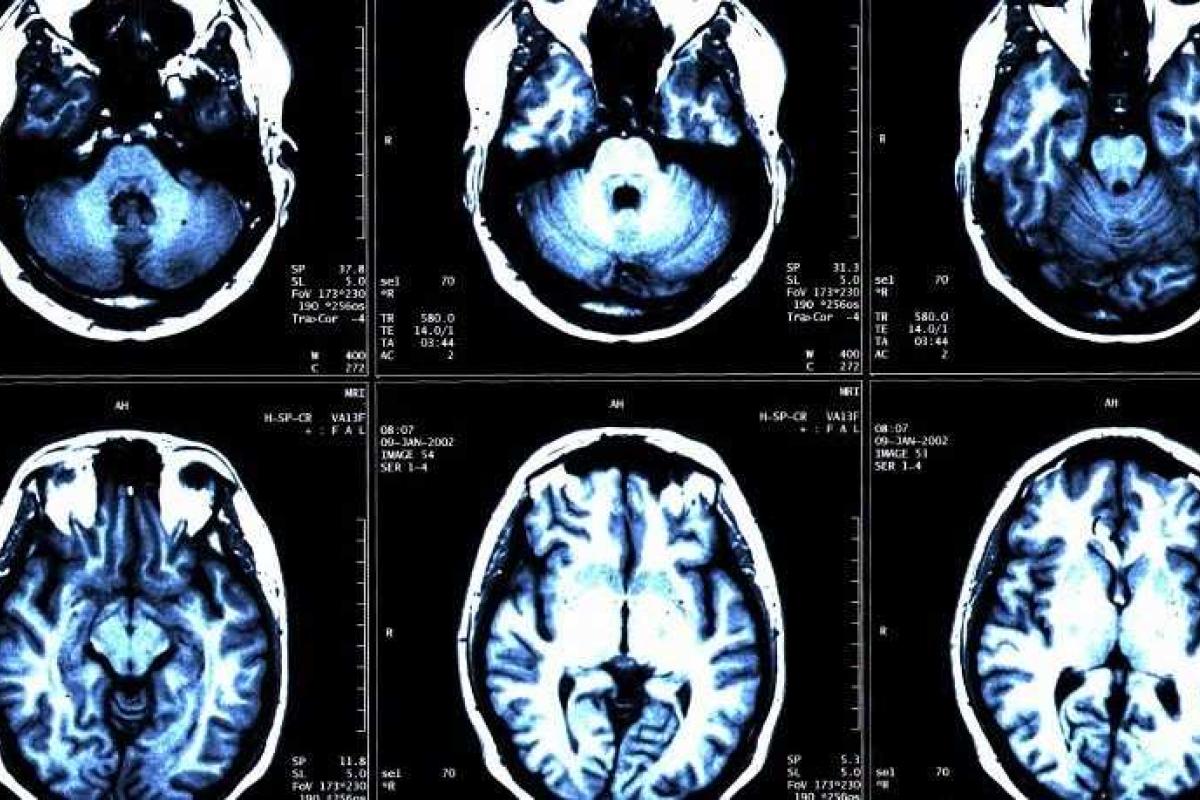

Однажды мужчина почувствовал слабость в ноге. Когда он обратился в больницу, невролог провел полную диагностику, включая исследование на аппарате МРТ.

На снимке было видно, что пациент потерял от 50 до 75 процентов объема мозга, при этом мужчина заверял весь персонал больницы, что чувствует себя прекрасно и не ощущал никаких изменений в состоянии своего здоровья, не считая проблемы с ногой.